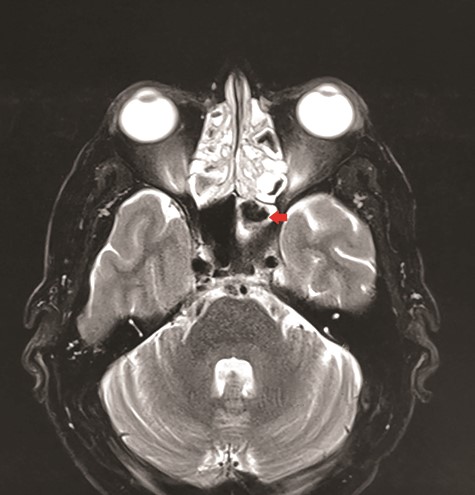

CT unveiled calcified densities within areas of hypoattenuation in the left sphenoid sinus. No marked bony destruction was observed (Fig. 2). A subsequent magnetic resonance imaging (MRI) was carried out to show hypodensity on T1 weighted post-contrast, and flow void in T2 weighted images within the same sinus (Figs. 3 and 4). Following informed consent, an emergency endoscopic left trans-ethmoidal sphenoidotomy was performed under general anaesthesia. A dense, darkened clay-like mass surrounded with the mucopurulent discharge was noticed within the left sphenoid sinus. The mucosa appeared inflamed and oedematous without clinical evidence of frank necrosis. The debris was utterly removed with a curette and sent for evaluation. The left sphenoid sinus was widened and thoroughly rinsed.

Axial view of MRI T1 weighted post-contrast showed hypodensity within the left sphenoid sinus with surrounding inflammation (red arrow).